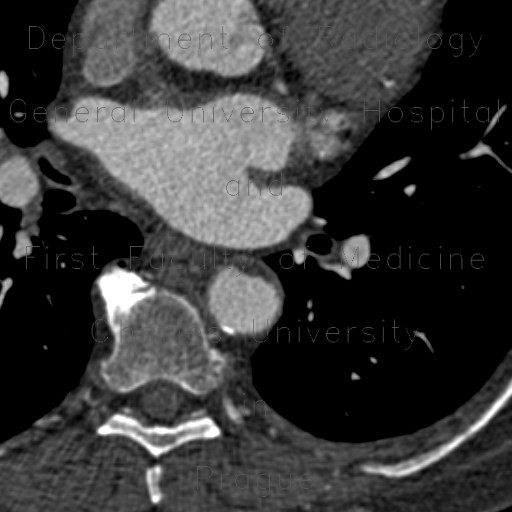

A penetrating atherosclerotic ulcer (PAU) is an atherosclerotic lesion that ulcerates, leading to a hematoma forming within the walls of the aorta. ... Read Article

Symptoms, risk factors and treatments of Penetrating atherosclerotic ulcer (Medical Condition) A penetrating atherosclerotic ulcer is an atherosclerotic lesion that ulcerates, leading to a hematoma forming within the walls of the aorta ... View Video

1120 AJR:174, April 2000 Tunick et al. Plaque Morphology and Plaque Thrombosis Ulceration.— In 1992, a landmark autopsy study examined the thoracic aorta of 500 pa- ... Fetch Doc

Fig. 1: A: Normal thoracic aortic blood flow characteristics in a healthy volunteer. Systolic filling of the ascending aorta (AAo), arch, descending ... Return Document